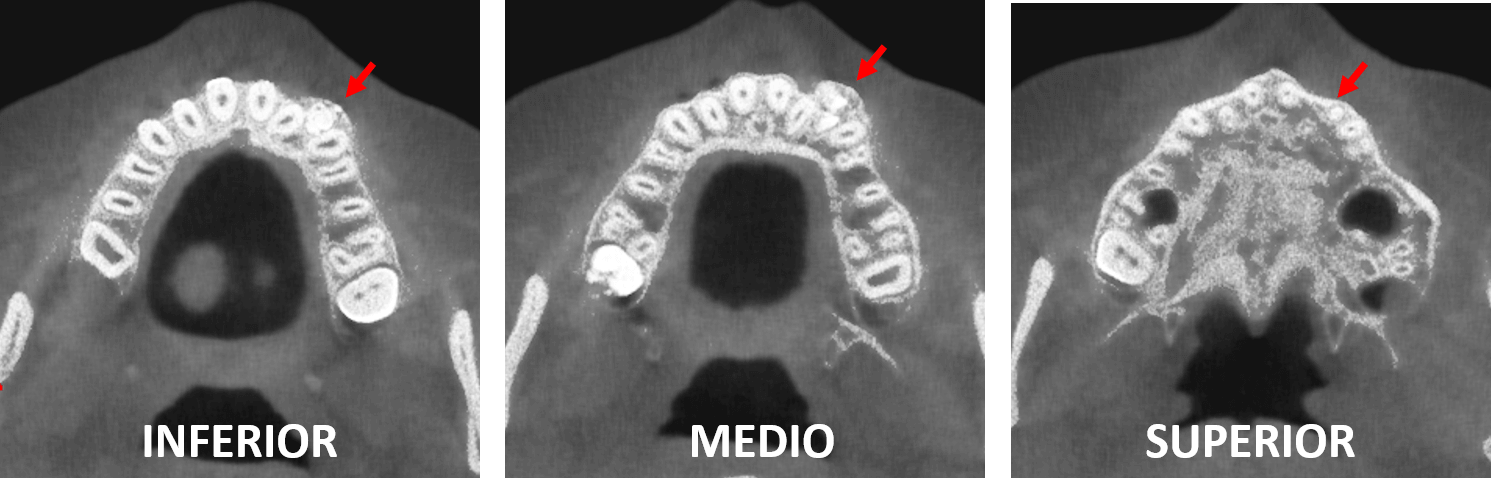

Fig.3

En cortes coronales (Fig.4) se observa un patrón de múltiples dentículos de la lesion señalada con flechas rojas: Nótese la diferencia ente las densidades donde se llega a identificar, densidades, semejantes a la del esmalte dentario, dentina y zonas hipodensas alargadas en el interior de los dentículos similares a la cámara pulpar y/o conductos radiculares. Se consideran signos tomográficos de un odontoma compuesto localizado en la parte anterior del maxilar superior.